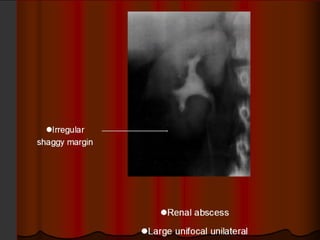

GU Tb-IVU

The most common findings being

hydrocalycosis,hydronephrosis, or hydroureter due to

stricture formation .

 Early signs include the moth-eaten appearance of

calyceal erosion and papillary irregularity- signs are

best seen on early excretory films.

Cavitary lesions communicating with the collecting

system are characteristic of TB.

 These lesions eventually enlarge as parenchymal

destruction ensues.

Fibrotic distortion of the collecting system and ureter

is also seen.